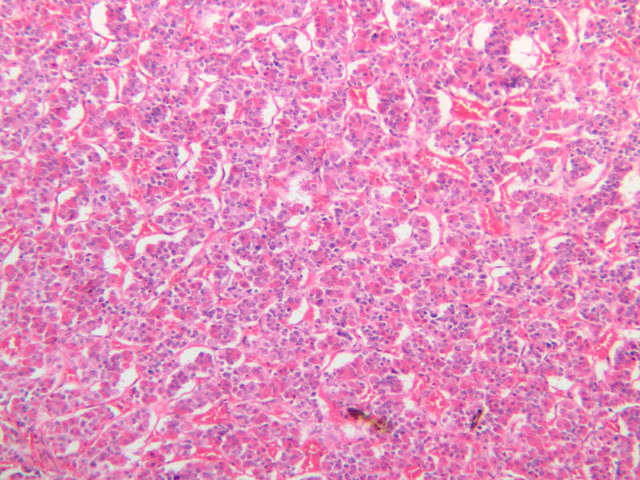

The adrenal gland (slide B-59, H&E [2.5x-labeled, 10x-labeled, 20x, 40x-labeled] [2.5x, 10x-labeled, 20x, 40x]; B-60, H&E [2.5x-labeled, 10x, 20x, 40x]; B-62, H&E [10x, 20x, 40x] [2.5x, 10x]) is a composite organ consisting of two functionally, structurally and embryologically different parts—an outer cortex and an inner medulla. Observe the gland at low power. Find the loosely organized tissue that comprises the medulla and the partially-separated columns of cells that make up the cortex. Scan the capsule and the tissue around it, looking for nerves and blood vessels. Study the pattern of cortical vasculature. In a pattern similar to that seen in the pars distalis of the pituitary, sinusoids run along the edges of columns or cords of cells. Owing to different arrangements of its constituent cells, the adrenal cortex has a layered appearance. From the capsule inward, these cortical layers are known as the zona glomerulosa, the zona fasciculata, and the zona reticularis.

The zona glomerulosa is located immediately beneath the capsule (B-60 adrenal gland, dog [10x, 20x] [20x, 40x]; B-59 [2.5x, 10x, 20x] [2.5x, 10x, 20x]). Its constituent cells are arranged in arcs or spheres, and, owing to their relatively small size, their nuclei appear to be close together. Cells of the zona glomerulosa secrete mineralocorticoids (e.g., aldosterone). The zona fasciculata consists of parallel columns or cords of cells that radiate toward the medulla and are separated by blood sinusoids (B-60 [2.5x, 10x, 20x, 40x]; B-62 [20x, 40x]). Owing to the extraction of lipids during histological processing, the cytoplasm of cells in the zona fasciculata appears highly vacuolated or "foamy". Cells of the zona fasciculata secrete glucocorticoids (e.g., hydrocortisone & cortisone) and some gonadocorticoids (weak androgens). The zona reticularis is the deepest cortical layer and lies adjacent to the medulla (B-60 [20x, 40x]; B-62 [20x, 40x]). It is characterized by irregular, interconnecting cords of cells which are separated by anastomosing capillary networks or sinusoids. Cells of the zona reticularis, which are smaller than those of zona fasciculata and do not contain as many lipid vacuoles, secrete gonadocorticoids and some glucocorticoids.